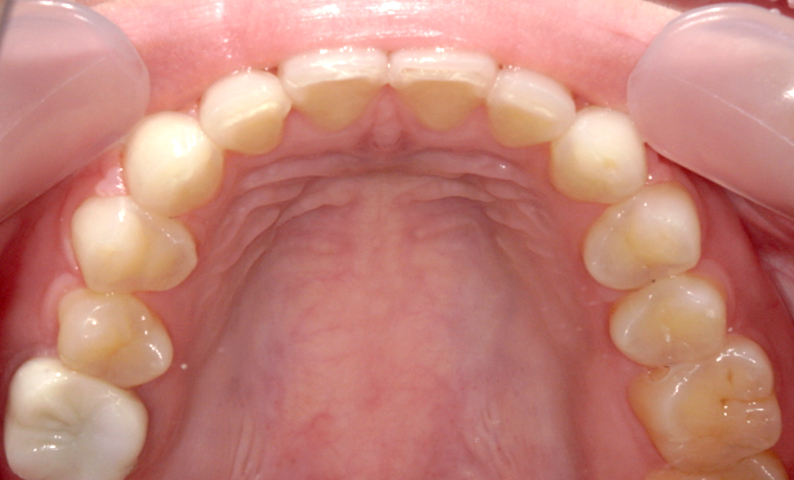

症例:上下顎の部分矯正

症例_009 前歯「八の字/V字型」症例

治療期間:11ヶ月金額:60万円+税40代女性八の字/V字型前歯のガタガタ捻転歯